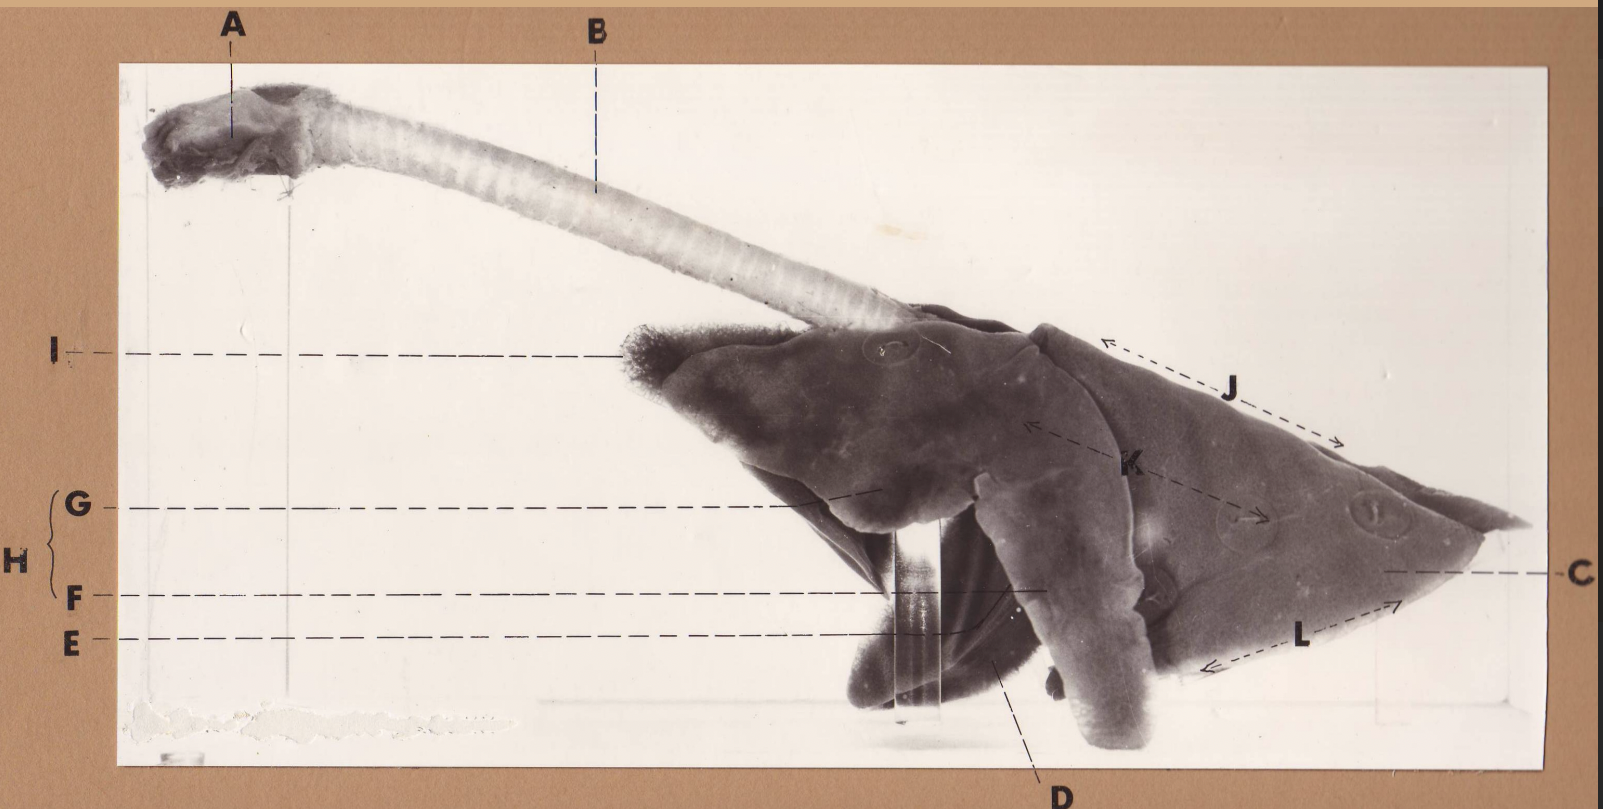

A

(cat larynx/trachea/lungs, L lateral)

larynx

B

(cat larynx/trachea/lungs, L lateral)

trachea

C

(cat larynx/trachea/lungs, L lateral)

caudal lobe

D

(cat larynx/trachea/lungs, L lateral)

middle lobe

E

(cat larynx/trachea/lungs, L lateral)

cardiac notch

F

(cat larynx/trachea/lungs, L lateral)

caudal segment, cranial lobe

G

(cat larynx/trachea/lungs, L lateral)

cranial segment, cranial lobe

H

(cat larynx/trachea/lungs, L lateral)

cranial lobe

I

(cat larynx/trachea/lungs, L lateral)

apex

J

(cat larynx/trachea/lungs, L lateral)

dorsal border

K

(cat larynx/trachea/lungs, L lateral)

costal surface

L

(cat larynx/trachea/lungs, L lateral)

basal border